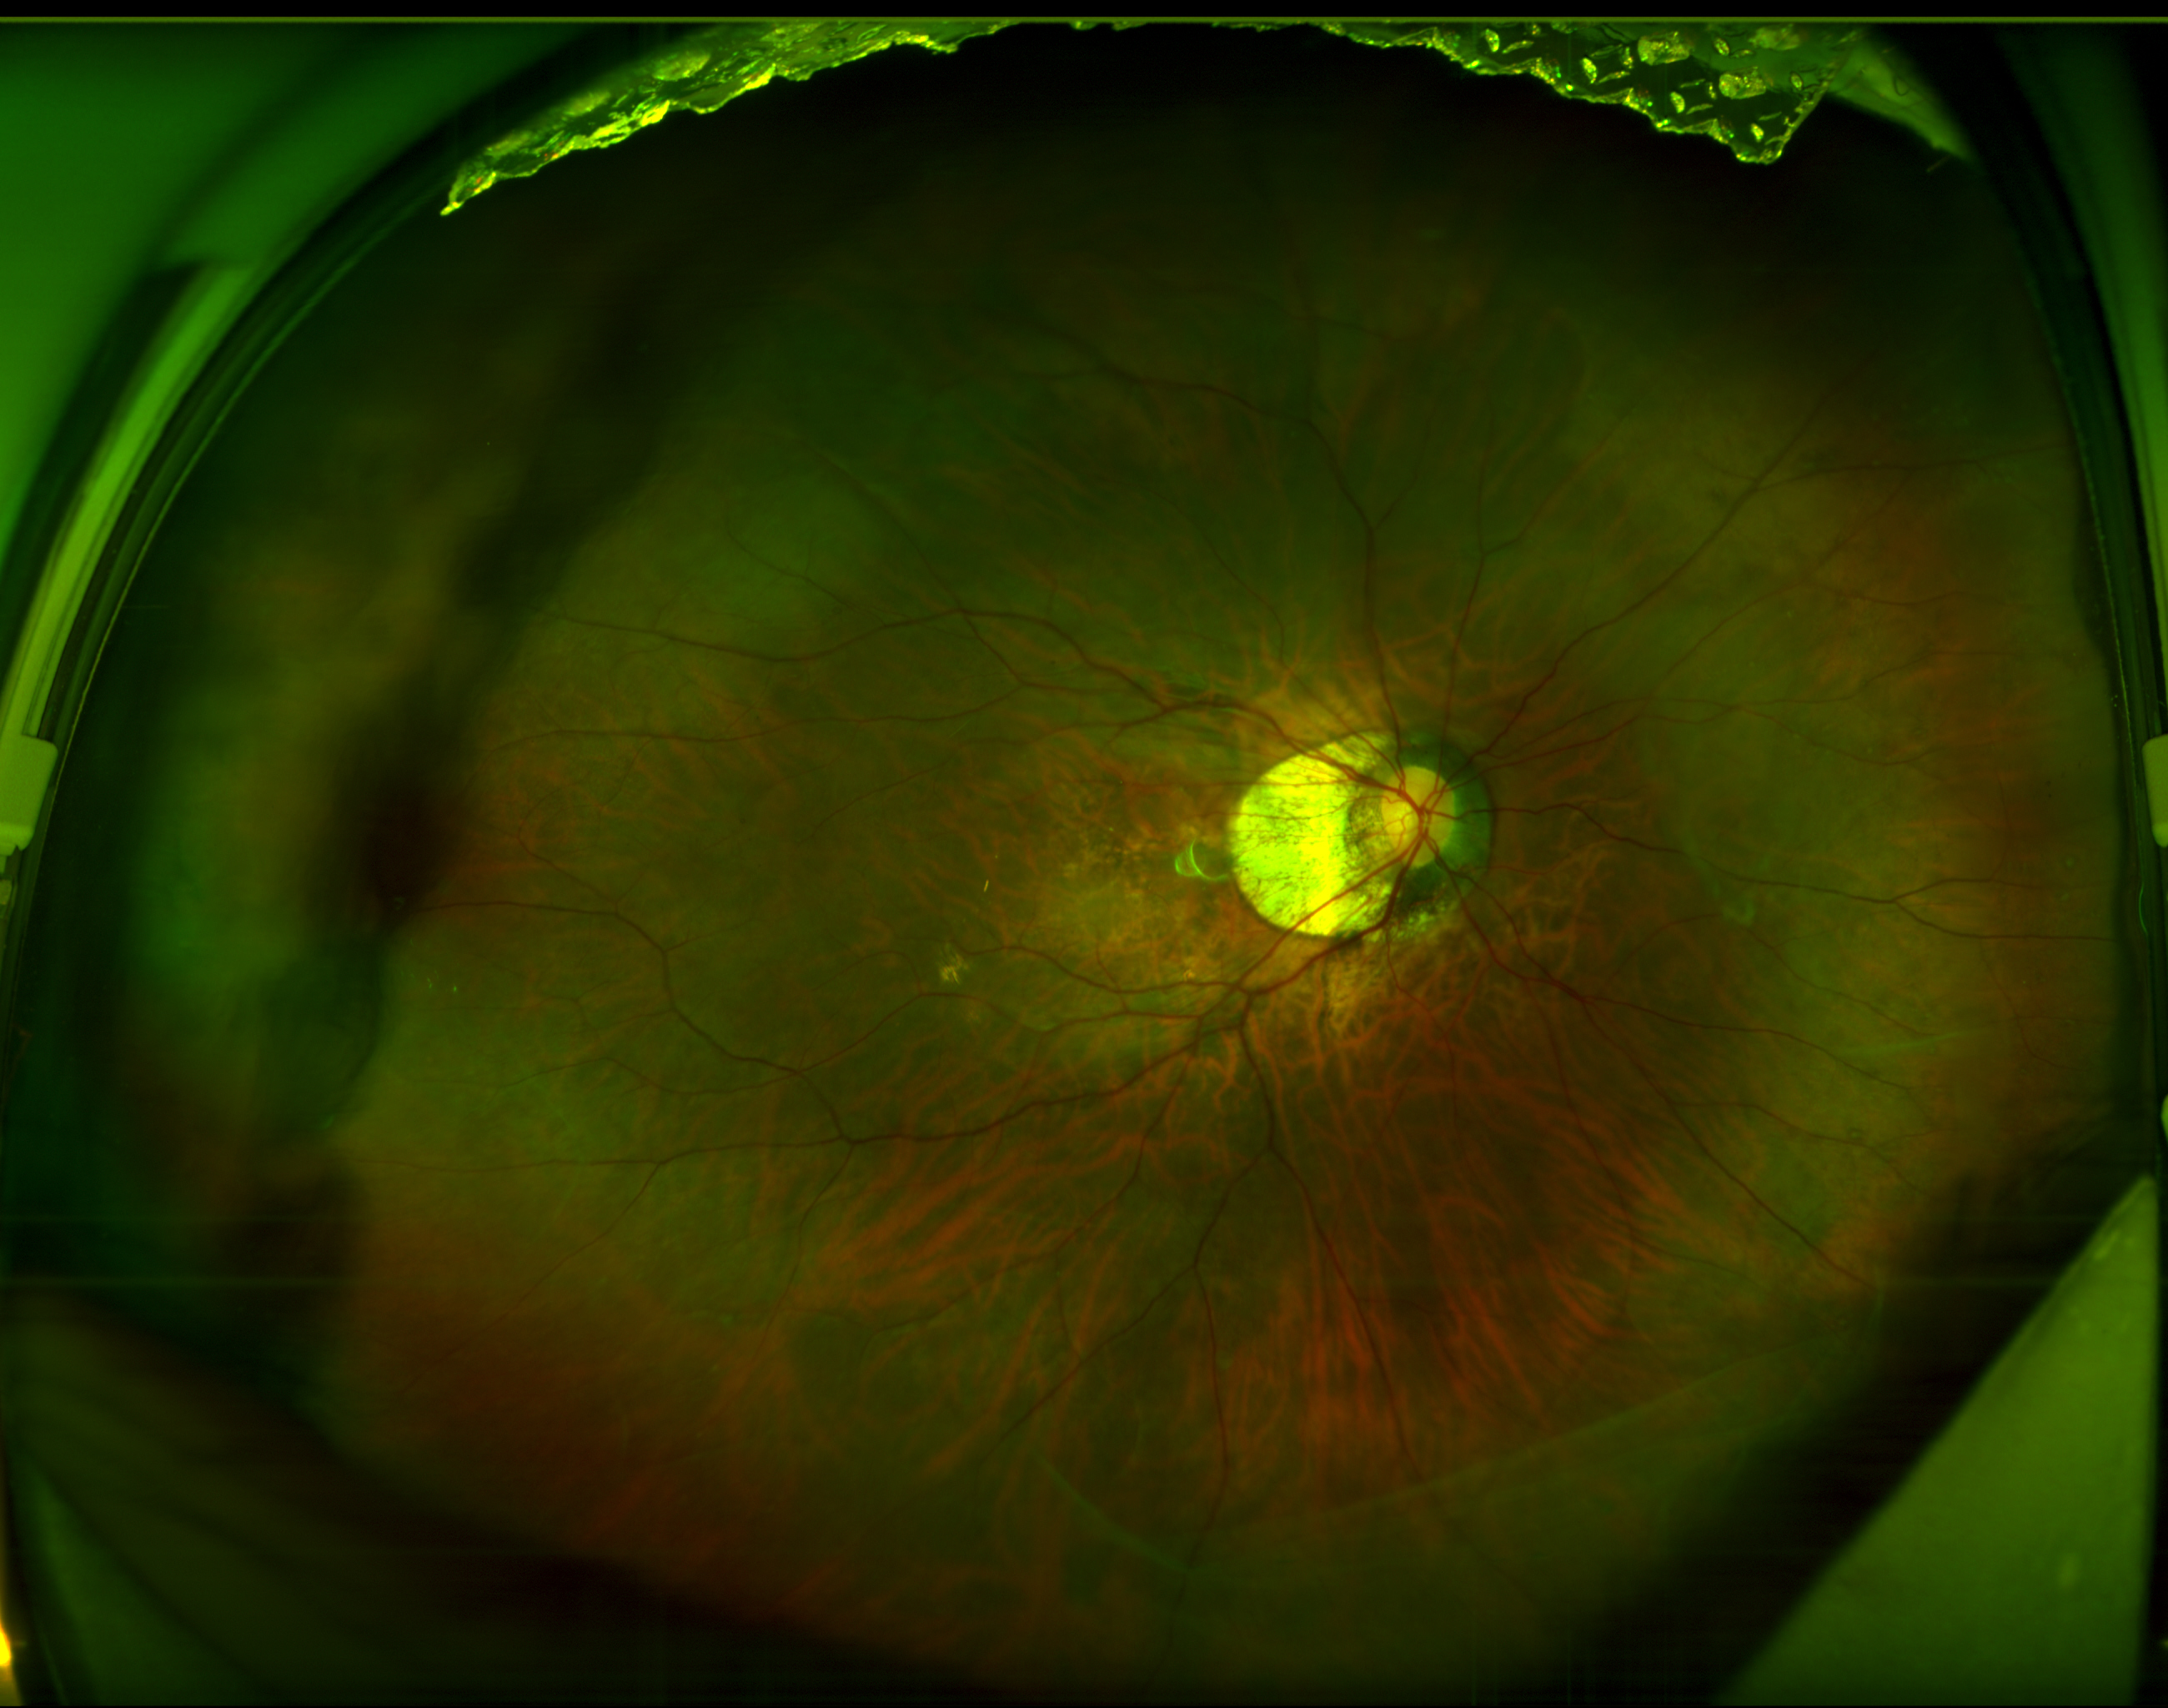

图:容阿姨术前(上)术后(下)眼底广角照相图

术后,容阿姨严格遵医嘱定期复查。12月8日,她再次专程从香港赶到深圳华厦眼科医院。复查结果令人惊喜,她的矫正视力不仅保住了0.8,还提升至 1.0,已经保持1年了!重新拥有了清晰正常的视界。